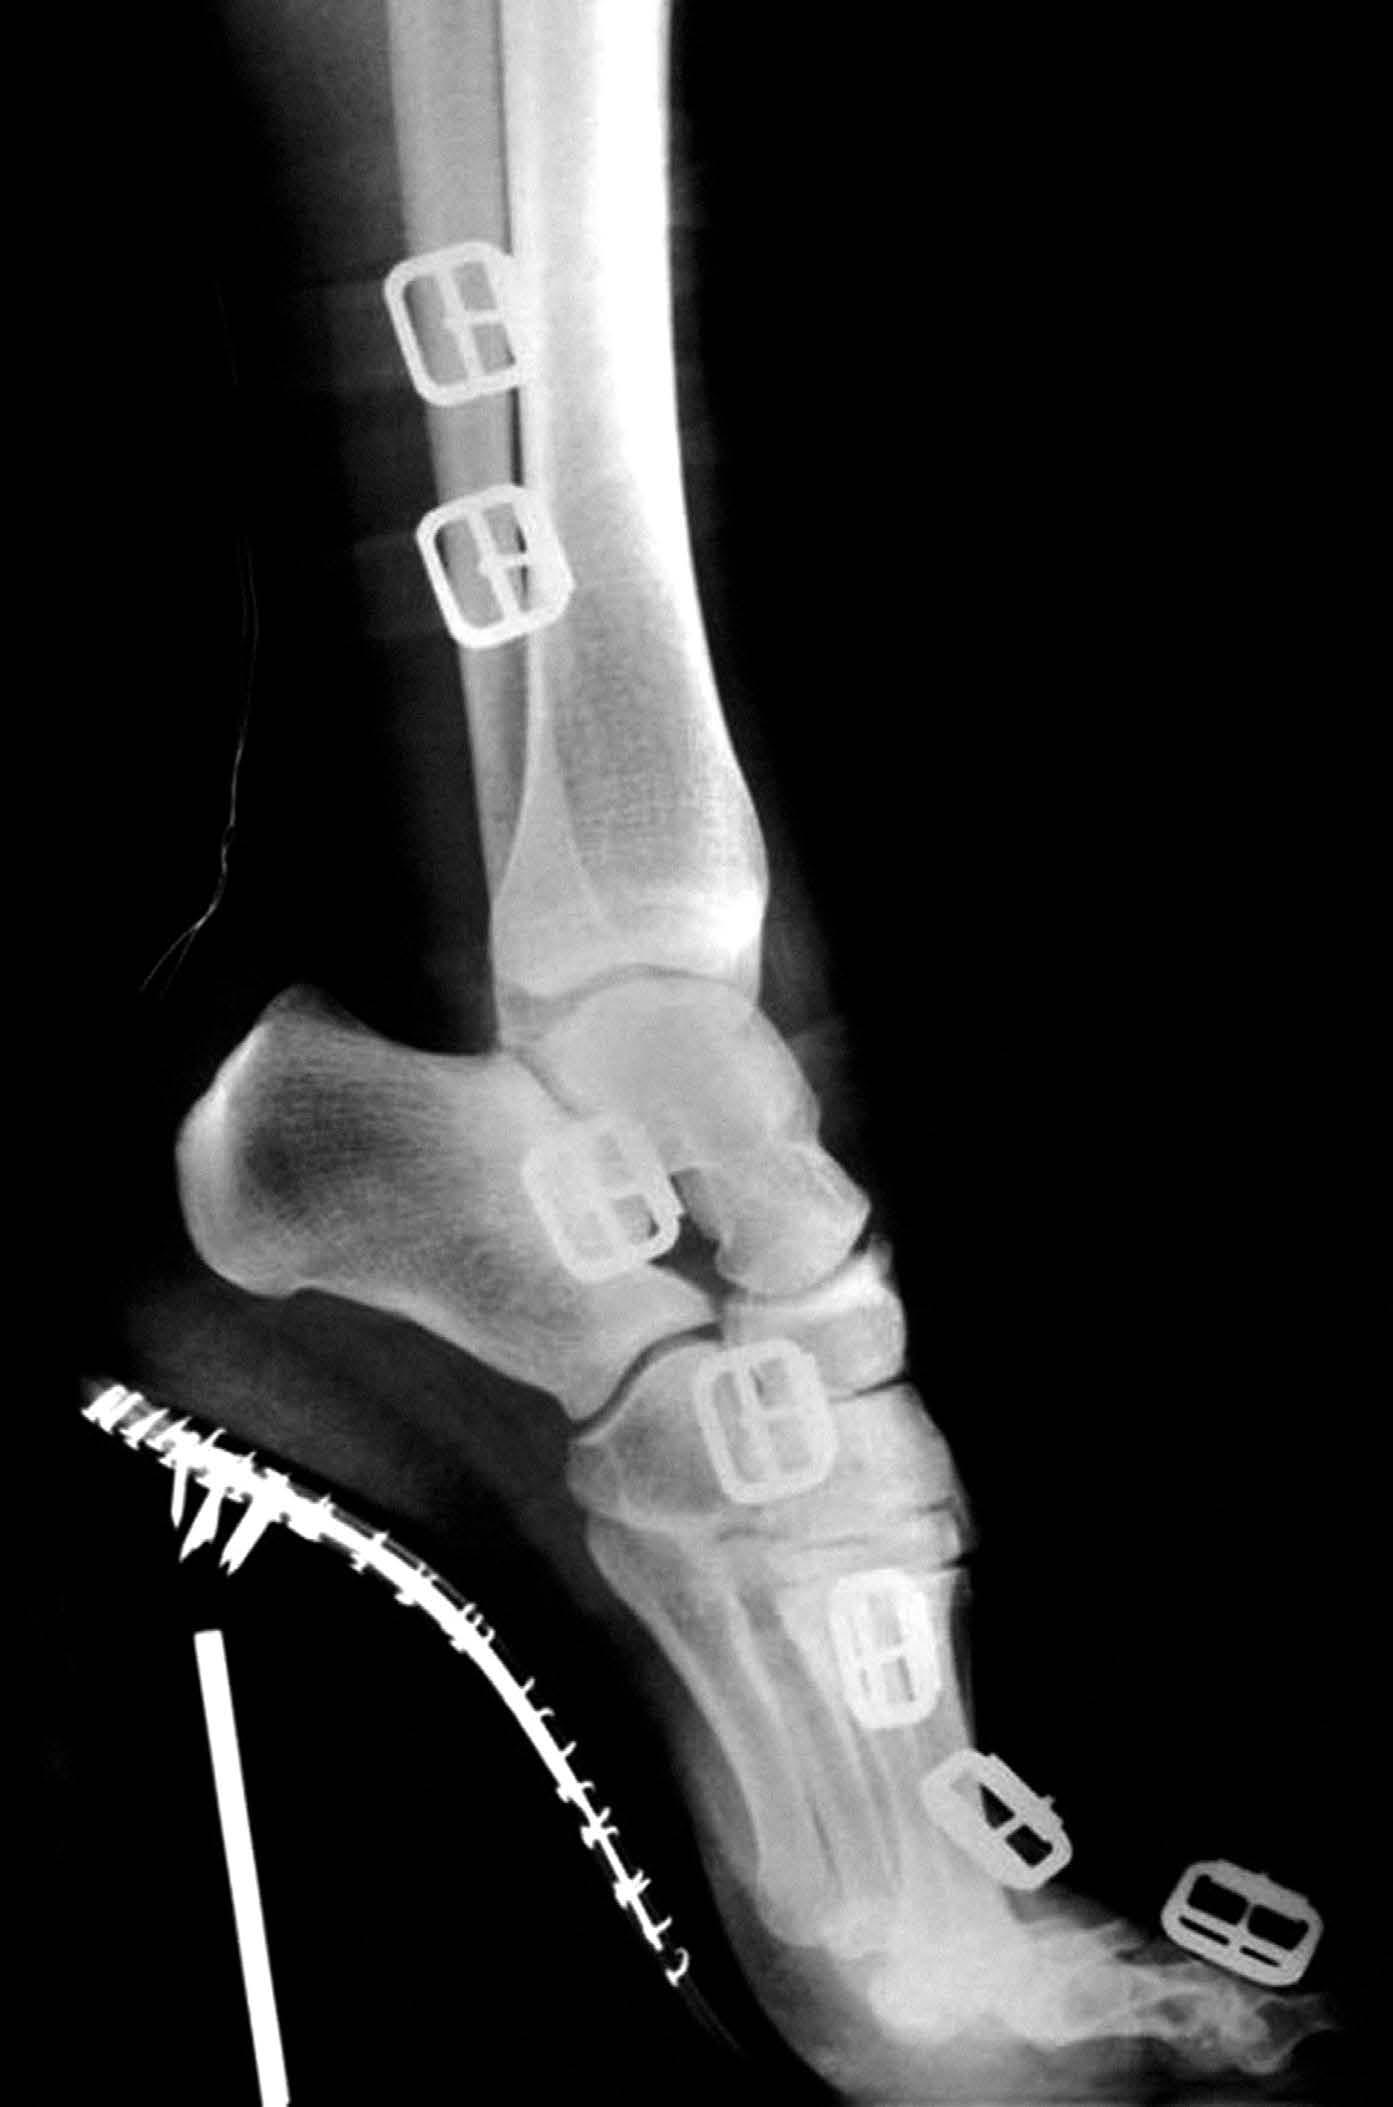

Das liegt auch daran, dass Medartis sein Produkt portfolio kontinuierlich ausbaut. Schon 2010 ist man mit der Fusschirurgie in das Geschäftsfeld der unteren Extremitäten eingestiegen. In den oberen Extremitäten kommen Implantatsysteme für den Ellbogen hinzu, etwas später auch solche für die Schulter. Das Ellbogensystem wurde von einem Designteam aus zehn Ärztinnen und Ärzten mitentwickelt und von den Chirurgen Prof. Dr. Lars Müller, Dr. Klaus Burkhart und Dr. William Geissler geprägt. Ergänzt werden diese Systeme von einer neuen Technologie: der patentrechtlich geschütz ten SpeedTip-Schraube (Seite 56 – 57). Deren selbstschneidendes Gewinde ist rasiermesser scharf, sodass die Ärzteschaft auf das Vorbohren des Knochens verzichten kann. Das spart Zeit im Operationssaal.